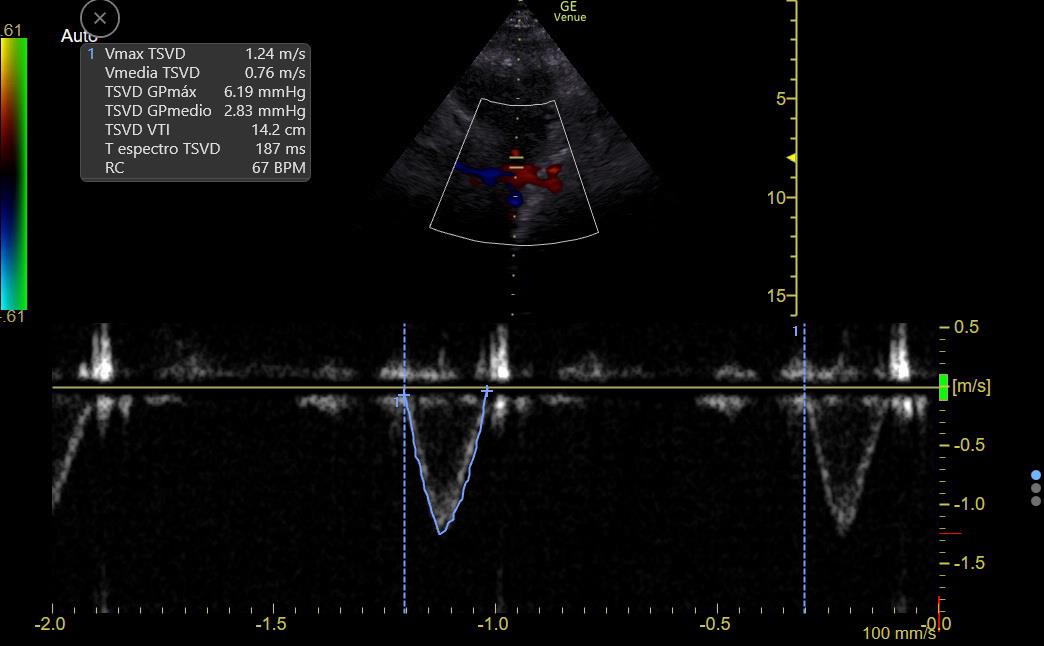

CO can be estimated by measuring flow at the LV or RV outflow tract:

RVOT Doppler shows ⬇️ VTI (9 to 14), so CO is LOW

There is ⬆️ respiratory variation: Low preload vs RV failure or Interdependence (Both Ruled out on #echofirst)

This suggests a low preload state